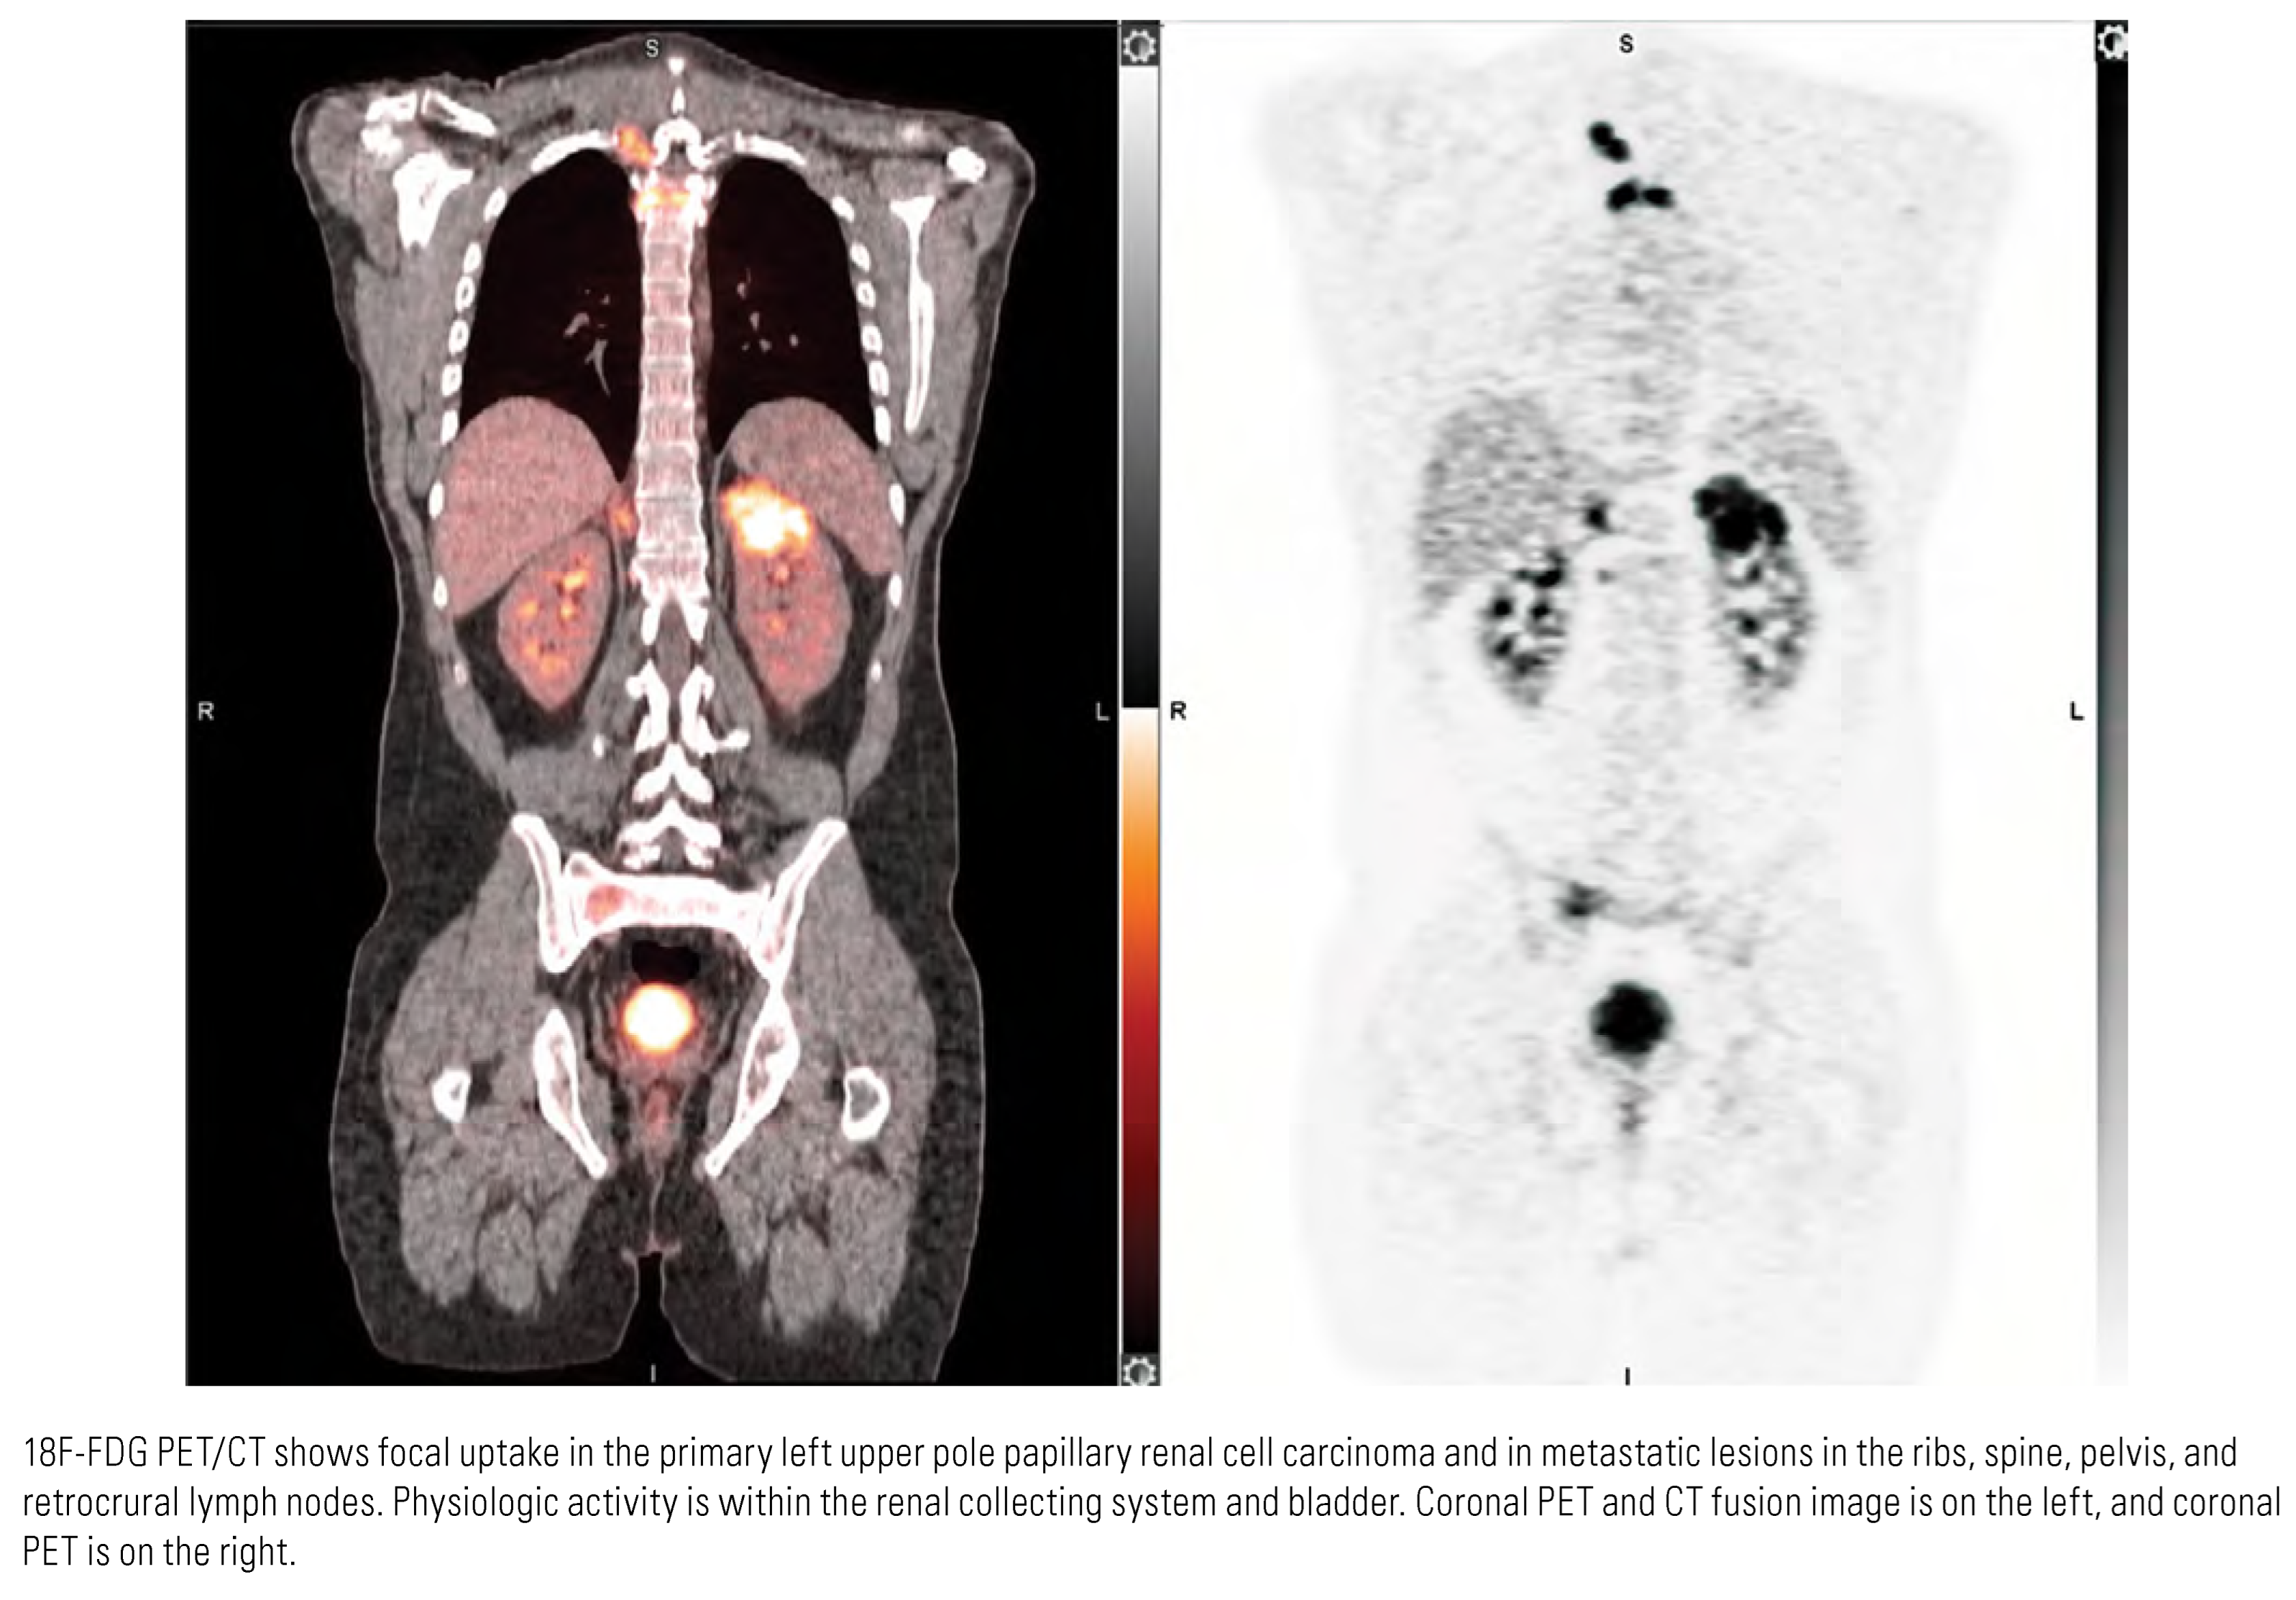

Evaluation of Nodes and Distant Metastases